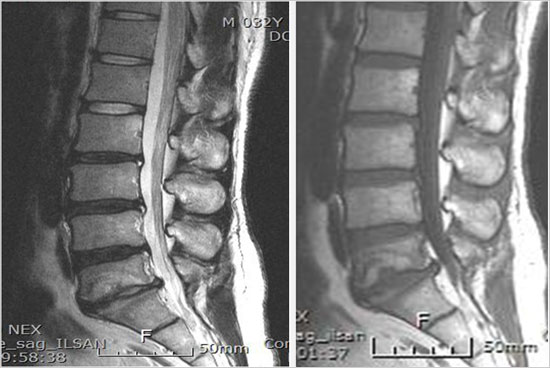

ôÃß°ü ÇùÂøÁõÀ̶õ?

ôÃß°üÀº ô¼ö(³ú±â´É°ú »çÁö, ¸öüÀÇ ±â´ÉÀ» ¿¬°áÇÏ´Â ±¸Á¶¹°)¸¦ º¸È£ÇÏ´Â ±¸Á¶¹°·Î¼­ ³ªÀ̰¡ µé¾î°¨¿¡ µû¶ó ôÃß¿¡¼­ µÎ °¡Áö º¯È­°¡ ¹ß»ýÇÏ°Ô Çϴµ¥ Çϳª´Â °ñ´Ù°øÁõ, ¶Ç ´Ù¸¥ Çϳª´Â ôÃß°ü ÇùÂøÁõÀ¸·Î¼­ ôÃß°ü ÇùÂøÁõÀº ÅðÇ༺ ôÃßÁúȯÀÔ´Ï´Ù.

°¡Àå Æ¯Â¡ÀûÀÎ Áõ»óÀº °£ÇæÀûÀÎ ½Å°æÀμº ÆÄÇàÀ̶ó°í ÇÏ¿© Ãʱ⿡´Â ¿À·¡ °ÉÀ¸¸é ÀåµýÁö°¡ ¾ÆÆÄ¿ÀÁö¸¸ ½ÉÇØÁö¸é ¹ö½ºÁ¤·ùÀå ÇϳªÀÇ °Å¸®µµ °ÈÁö ¸øÇÏ¿© ½¬¾ú´Ù °¡¾ßÇÏ¸ç ¾ÆÁÖ ½ÉÇÑ °æ¿ì´Â ¼­ ÀÖ´Â °Í Á¶Â÷ Èûµé¾îÇÏ°Ô µÇ¾î Á¤»óÀûÀÎ º¸ÇàÀÌ ¾î·Æ°Ô µË´Ï´Ù. ƯÈ÷ Ãß°£ÆÇ Å»ÃâÁõ°ú µ¿¹ÝµÇ´Â °æ¿ì¿¡´Â ´Ù¸®ÂÊÀÇ Àú¸²Áõ»ó°ú ´ç±â´Â Áõ»óÀÌ ´õ¿í ½ÉÇÏ°Ô ³ªÅ¸³ª°Ô µË´Ï´Ù.

* ¼ö¼úÀû Ä¡·á : À§¿Í °°Àº º¸Á¸Àû Ä¡·á¿¡µµ È¿°ú°¡ ¾øÀÌ ½ÉÇÑ ÅëÁõ ȤÀº ºÎºÐÀû ½Å°æ¸¶ºñµîÀÇ Áõ»óÀÌ ÀÖÀ¸¸é ¼ö¼úÀû Ä¡·á¸¦ ¿äÇÕ´Ï´Ù. ½Å°æÀ» ¾Ð¹ÚÇÏ´Â ±¸Á¶¹°ÀÎ »À³ª ¿¬ºÎ Á¶Á÷À» Á¦°ÅÇÏ´Â °¨¾Ð¼ú ÈÄ Ã´ÃßÀ¯ÇÕ¼úÀ» ½ÃÇàÇϴµ¥ ôÃß°æÀ» ÅëÇÑ ³ª»ç ¸ø °íÁ¤ ¹× »ÀÀ̽ļúÀ» ÇÏ´Â ¹æ¹ý°ú ôÃßü »çÀÌ¿¡ Àΰø ³»°íÁ¤¹°À» »ðÀÔÇÏ¿© À¯ÇÕ½ÃŰ´Â ¹æ¹ýµîÀÌ ÀÖ½À´Ï´Ù. ±×¸®°í ÇùÂøÀÌ ½ÉÇÏÁö ¾ÊÀº °æ¿ì¿¡´Â Çö¹Ì°æÀû ôÃß°ü °¨¾Ð¼ú ·Î¼­ ºñ±³Àû °£´ÜÈ÷ ¼ö¼úÇÏ´Â ¹æ¹ýµµ ÀÖ½À´Ï´Ù